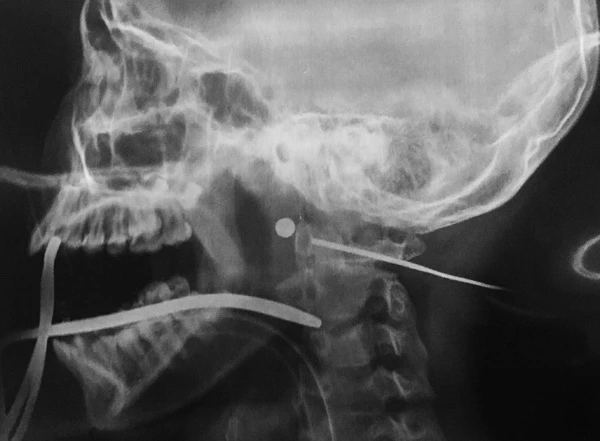

Trước đó bệnh nhi nhập viện trong tình trạng vết thương ở mang tai đang rỉ máu. Qua khám lâm sàng và kết quả chẩn đoán hình ảnh cho thấy viên đạn hình tròn đi xuyên từ mang tai và đang nằm sâu gần cột sống cổ. Các bác sĩ dự đoán vết thương do súng tự chế gây ra.

Qua chẩn đoán hình ảnh xác định viên đạn hình tròn nằm trong cổ của bệnh nhi.